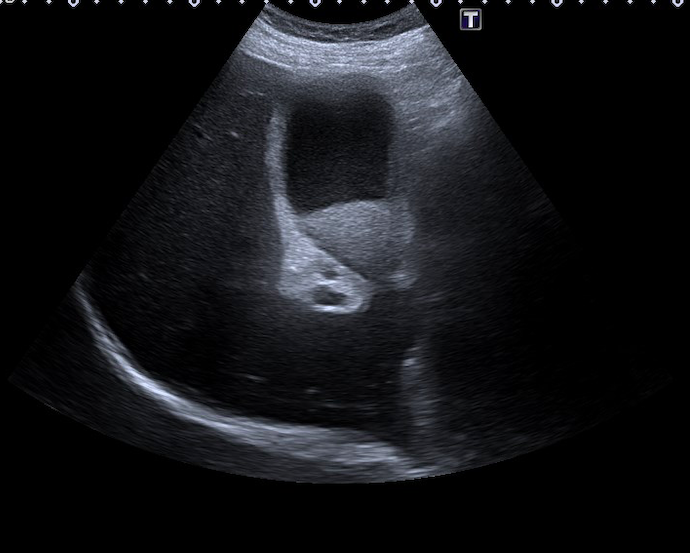

Se realiza una exploración abdominal, donde se objetiva distensión de la vesícula biliar, con un diámetro longitudinal de 10 cm, y engrosamiento de la pared de 4 mm (figura 1), abundante barro biliar (figura 2) y la presencia de una litiasis en cuello vesicular (figura 3). Murphy ecográfico positivo. Doppler negativo, sin dilatación de la vía biliar (figura 4). No líquido perivesicular. Resto de rastreo sin alteraciones.